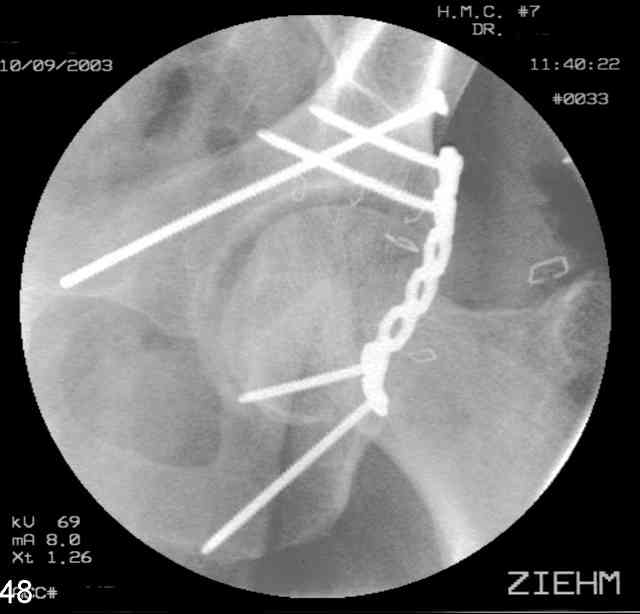

12.Prone Obturator-Outlet

Same with a contoured pelvic reconstruction plate applied and tensioned.

Prone Iliac Oblique

The other oblique reveals the extra-articular implants.... you know the AC screw is extra-articular from the other views.